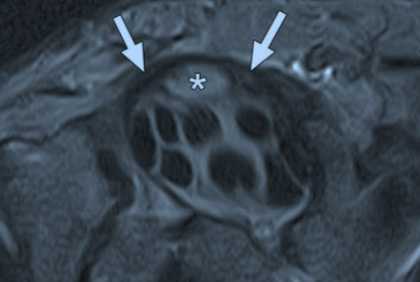

МРТ запястья. Аксиальная Т2-взвешенная МРТ. Отек медианного нерва и утолщение ретинакулум.